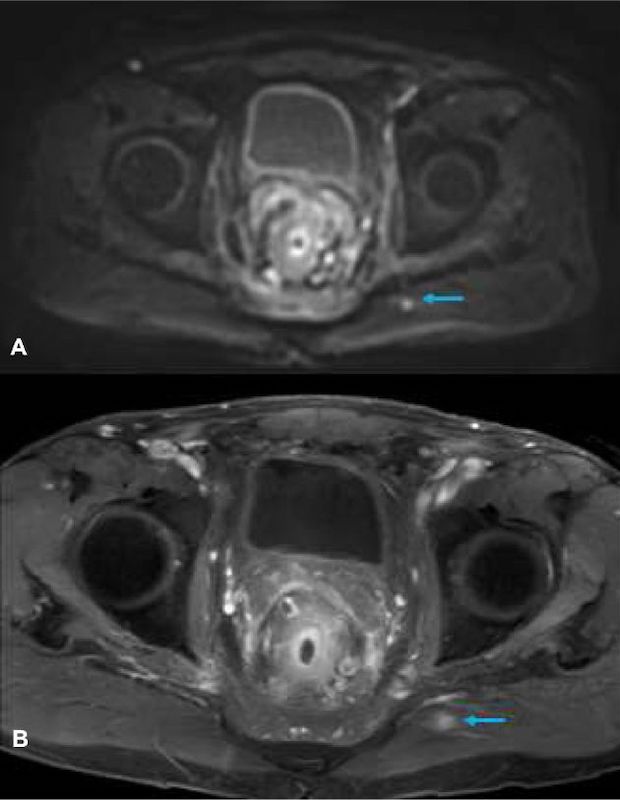

3T MRI is recommended over 1.5T for visualization of the prostate and colorectal area. Higher quality images are obtained providing colorectal surgeons and urologists with the detailed imaging needed for proper diagnosis. Benefits of 3T MRI are the ability to obtain images demonstrating miniscule slice thicknesses as low as 1mm to aid in diagnosis of difficult and complex cases.

MRI uses radio waves to produce detailed imaging, and there is no ionizing radiation exposure to the patient. The images investigate the cause of pain or swelling, examine lymph nodes and other large organ systems. MRI can aid in the diagnosis, location and the stage of cancer based on the spread of cancer to other organs.